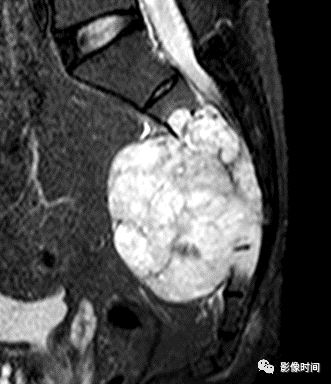

(二)瘤软骨  为肿瘤细胞产生的软骨基质,多来源于软骨类肿瘤,或内有化生瘤软骨成分的其他肿瘤如成软骨型骨肉瘤。瘤软骨为软组织密度,未钙化时,主要通过 MRI 检查显示。

由于瘤软骨多由富含水分及粘多糖的透明软骨构成,故 T1WI 呈偏低信号,T2WI 或 PDWI 呈明显高信号,被低信号的纤维间隔分开呈分叶状(图 24、图 25a-b),增强扫描多呈不均匀分隔状强化(图 25c),主要是纤维间隔强化,瘤软骨强化不明显之故。

图 24  瘤软骨:内生软骨瘤

图 25  瘤软骨:内生软骨瘤